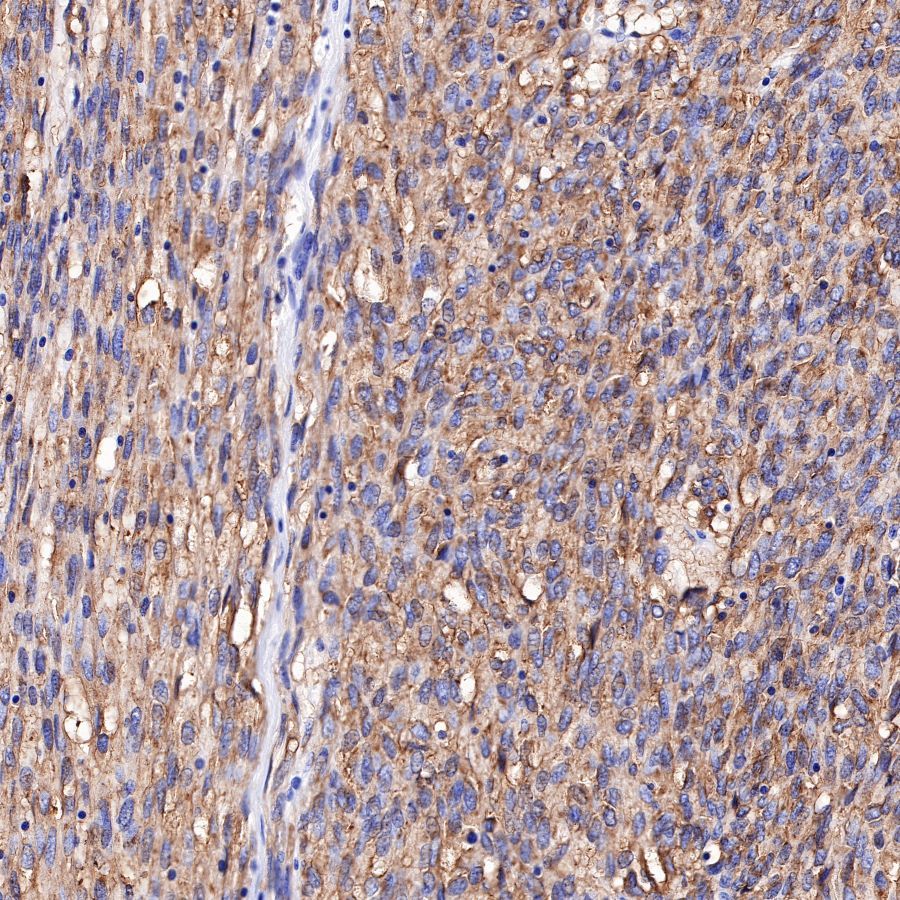

IHC shows positive staining in paraffin-embedded human lung cancer.

Anti-CD117 antibody was used at 1/1000 dilution, followed by a Goat Anti-Rabbit IgG H&L (HRP) ready to use.

Counterstained with hematoxylin.

Heat mediated antigen retrieval with Tris/EDTA buffer pH9.0 was performed before commencing with IHC staining protocol.